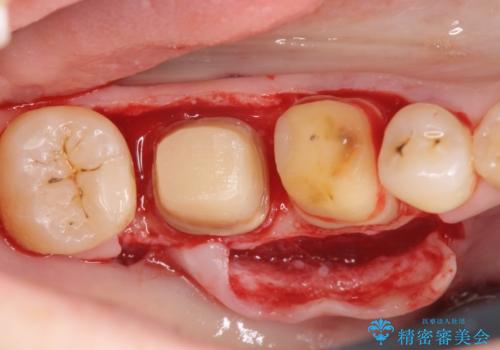

歯周ポケットの除去を併用したセラミック治療

適合や審美性に優れるセラミック治療を行う前に、歯周病の問題を歯周外科を行うことで解決し将来的に不安のないような口腔内環境を整備していきます。

- 110万円(ジルコニアクラウン×6・仮歯×6 歯周外科×2)費用は治療当時の料金となります

治療前に4-5mm程度あった歯周ポケットは全て2mm以内となり、非常に清掃性が高く、歯周病の再発しずらい環境に整えた上でのセラミック治療を実践することができました。